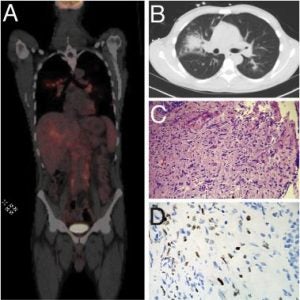

An avant-garde study of the uncommon KSHV-associated inflammatory cytokine syndrome. This paper was newly published in the Virology Journal at the beginning of this month.